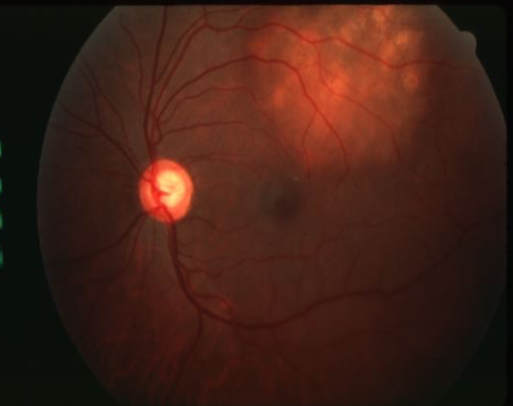

solitary choroidal hemangioma

choroidal hemangioma

choroidal hemangioma

choroidal hemangioma

choroidal hemangioma

choroidal hemangioma

choroidal hemangioma

unilateral, benign vascular tumor

no sexual or racial predilection

not a cancer

does not metastasize

appearance:

can be well circumscribed or diffuse

unilateral VA loss in adulthood (or incidental finding)

tumors compromised of blood vessels

smoothly elevated, dome-shaped (NOT mushroom shaped)

oval/circular shape

most common location is posterior pole

most 3-9mm in diameter

can cause CME, exudative RD, & secondary glaucoma

B-scan: sharp borders, acoustic solidity

FA: not pathognomonic

usually none unless subretinal fluid threatens macular region

laser photocoagulation if VA threatened due to serous RD